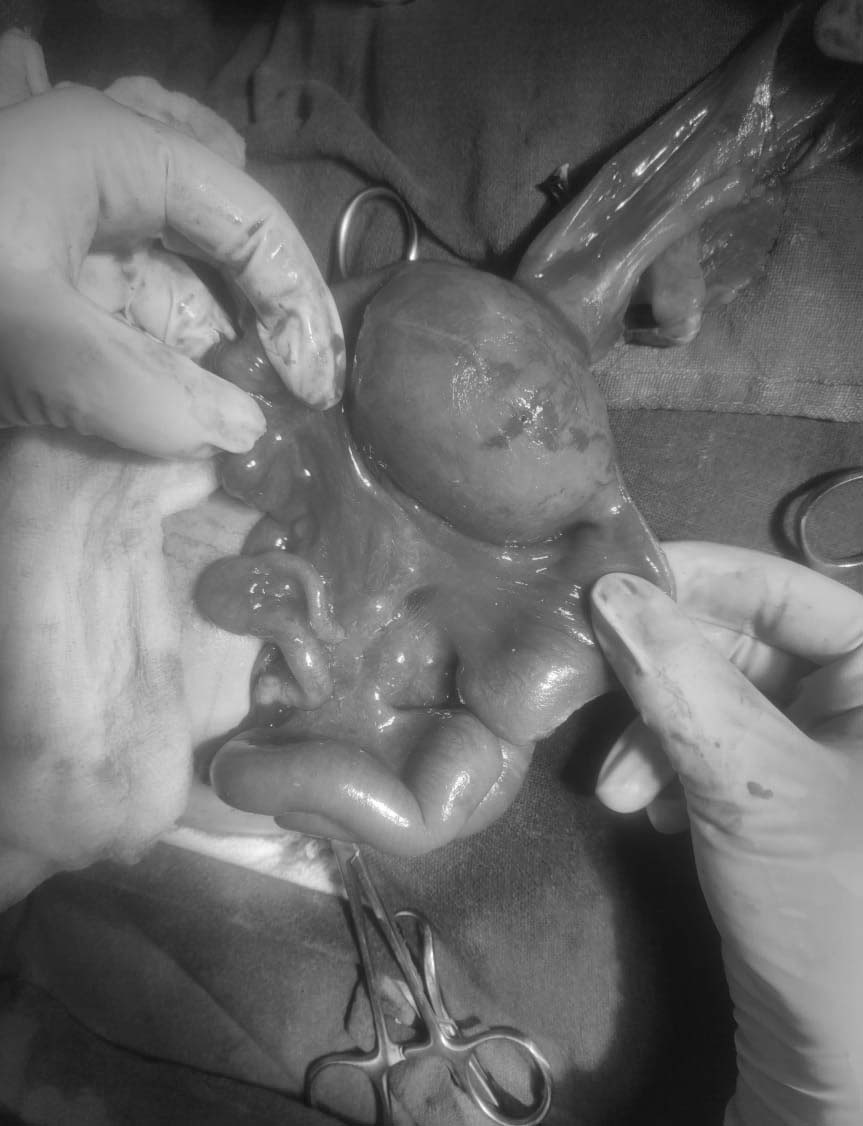

अस्पताल भर्ना भएको चार दिनपछि गत असार १२ गते पहिलो र त्यसको चार हप्तापछि साउन ९ गते दोस्रो शल्यक्रिया गरिएको थियो । पेडियाट्रिक सर्जन डा.गिरीका अनुसार उक्त शिशुको नाईटोको भाग नबनेको र सोही ठाउँबाट आन्द्रा बाहिर निस्किएको थियो । डा. गिरीले भन्नुभयो “आन्द्रा समेत फुलेको अवस्थामा रहेको यस्तो प्रकृतिका घटना दुर्लभ हुने गर्दछ ।” डा. गिरीका अनुसार एकदेखि दुई लाख शिशुहरुमा मात्रै यस्तो समस्या आउने गर्दछ ।

डा.गिरीले कान्तिपुर हेल्थसँग भन्नुभयो “नाईटो नबेको, आन्द्रा बाहिर आएको र आन्द्रा फुटेको अवस्था लाखौंमा एक जनामा देखिन्छ । यो निकै दुर्लभ समस्या हो ।” उहाँले अगाडि थप्नुभयो “सानो आन्द्रा यसरी फुलेर बस्नु आफैमा दुर्लभ हो ।” यस्तो समस्यालाई ओमफालोसियल (Omphalocele) भनिने उहाँको भनाई छ ।

शिशुको मांसपेशी पूर्ण रुपमा विकास नभएकोले बाहिर निस्किएको आन्द्रा एकै पटक भित्र नअटाउने भएकाले दुई पटक गरेर शल्यक्रिया गर्नु परेको डा. गिरीले बताउनुभयो । उहाँले भन्नु “धेरैजसोमा एउटै शल्यक्रियाले हुन सक्छ । नाईटो नै नभएको, पेटमा प्वाल परेर आन्द्रा बाहिर आएको, प्वाल धेरै साँघुरो र सानो भएकाले बाहिर आएको आन्द्रा कस्सिँदै जान्छ ।” यस्तो अवस्थामा दुई पटक गरेर शल्यक्रिया गर्ने पर्ने डा.गिरीले बताउनुभयो । उहाँले अगाडि थप्नुभयो “कस्सिंदै गएर आन्द्रामा रक्तसञ्चार नभएर कालो हुन सक्ने सम्भावना थियो । कतिपय समस्या तुरुन्तै शल्यक्रिया नगरी पनि राख्न सकिन्छ । तर उसको प्वाल धेरै साघुरो भएको हुँदा आन्द्रा फुल्दै गएको थियो । त्यही भएर छिटो शल्यक्रिया गर्नु परेको हो ।”

फुलेको आन्द्राको ८ सेन्टिमिटर काटेर पुनः जोडिएको जानकारी दिंदै डा. गिरीले आन्द्रा अलिअलि निलो भईसकेको बताउनुभयो । उहाँले अगाडि भन्नुभयो “निलो भएको भाग ठीक होस् भनेर सानो आन्द्राको भाग काटेर बाहिर निकालेर राख्यौं । जसमा कृतिम मलद्वार बनाईयो । अर्थात् त्यहीबाट दिसा बाहिर निस्कने गरी व्यवस्था गरियो । जसले गर्दा जोडेको आन्द्रा छिटो निको हुने पाओस् भनेर यस्तो गरियो ।”

दोस्रो शल्यक्रियामा बाहिर निकालेर राखिएको कृतिम मद्वार सहितको आन्द्रालाई भित्र जोडेर राखिएको डा. गिरीले बताउनुभयो । नाईटो समेत नबनेको उक्त शिशुको नाईटो बनाईएको छ । ४२ दिन अस्पतालमा राखेर उपचारपछि उक्त शिशु अहिले डिस्चार्ज भईसकेका छन् । अहिले शिशुको स्वास्थ्य राम्रो रहेको डा. गिरीले बताउनुभयो ।